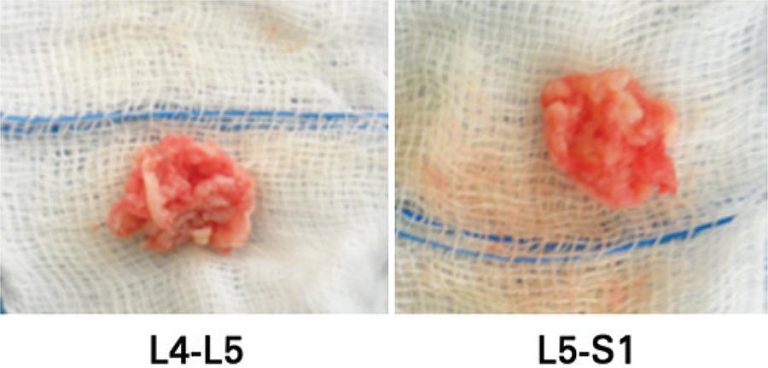

Apophyseal ring fractures are rare injuries that may be associated with lumbar disc herniation in young patients. We report a unique case in the literature of a 15-year-old male patient who played football and was admitted at our service complaining of sciatica radiating into the left leg. An apophysial ring injury of L5 vertebral body was observed. This injury caused two extruded disc herniation in adjacent levels. Surgical procedure was indicated after failure of conservative treatment.

Keywords: Case reports; Intervertebral disc displacement/diagnosis; Intervertebral disc displacement/surgery; Spinal fractures/diagnosis; Spinal fractures/surgery